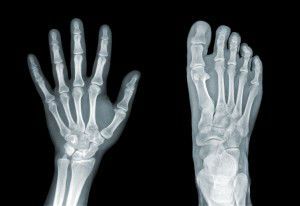

The term “bone fat” refers to the fat content of bone marrow, the tissue found within our bones. Bone marrow is home to a variety of cells, including blood and immune cells. It also has fat content, which can vary in concentration over time, and may be altered by lifestyle factors.

Dr. Styner notes that research has observed that more bone fat is produced by mesenchymal stem cells within the bone as a person ages, and it is hypothesized that this increased production of bone fat is a factor in older people’s susceptibility to bone fractures.

An earlier study, published in 2013 in the journal Radiology, analyzed the bone fat content of over 100 obese adults (between the ages of 19 and 45) with no other health issues, and found that the individuals with higher levels of muscle and liver fat also had higher levels of bone marrow fat. The researchers concluded that high levels of fat in the bone marrow increased an individual’s risk of bone fracture.

Lead author Dr. Miriam Bredella summarizes, “bone marrow fat makes bones weak. If you have a spine that’s filled with fat, it’s not going to be as strong.”